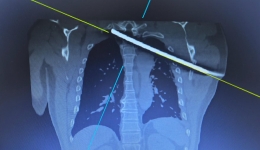

• 今日头条:钢筋穿胸命悬一线 四川省人民医院多学科专家协作挽救患者生命 媒体报道

今日头条:钢筋穿胸命悬一线 四川省人民医院多学科专家协作挽救患者生命

近1厘米粗的螺纹钢自左腋下刺入,沿胸腔走行后紧贴主动脉弓,进一步穿过胸椎管,行径与脊髓近乎“零距离”,稍有不慎即可引发致命大出血或不可逆神经损伤。这样的伤者会有多大的生存希望?11月17日夜,四川省人民医院骨科联合急救中心、胸外科、麻...

• 四川观察:男子遭钢筋穿胸 省医院多学科联合开展“毫米级”手术 媒体报道

四川观察:男子遭钢筋穿胸 省医院多学科联合开展“毫米级”手术

小指粗的螺纹钢筋自左腋下刺入,斜向横穿整个胸腔直达右侧肩颈部皮下,行径与脊髓近乎“零距离”,这样的伤者会有多大的生存希望?近日,四川省人民医院多学科团队,联合开展了一台高难度“毫米级”手术。

• 钢筋穿胸命悬一线,我院多学科专家协作挽救患者生命 院内新闻

钢筋穿胸命悬一线,我院多学科专家协作挽救患者生命

近1厘米粗的螺纹钢自左腋下刺入,沿胸腔走行后紧贴主动脉弓,进一步穿过胸椎管,行径与脊髓近乎“零距离”,稍有不慎即可引发致命大出血或不可逆神经损伤。这样的伤者会有多大的生存希望?11月17日夜,我院骨科联合急救中心、胸外科、麻醉科、手术...

• 钢筋穿胸命悬一线,我院多学科专家协作挽救患者生命

• 今日头条:钢筋穿胸命悬一线 四川省人民医院多学科专家协作挽救患者生命

• 四川观察:男子遭钢筋穿胸 省医院多学科联合开展“毫米级”手术